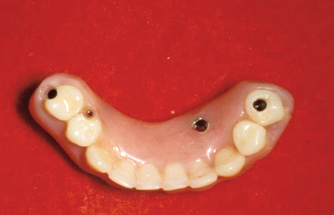

Fig 15. This all-resin interim restoration, which served as a fixed long-term provisional for more than 5 years, is an example of an entry-level option that offers the physiologic benefits of a long-term fixed restoration but with an economic equivalence to a mandibular two-implant overdenture.

Figure 15

Fig 16. This all-resin interim restoration, which served as a fixed long-term provisional for more than 5 years, is an example of an entry-level option that offers the physiologic benefits of a long-term fixed restoration but with an economic equivalence to a mandibular two-implant overdenture.

Figure 16